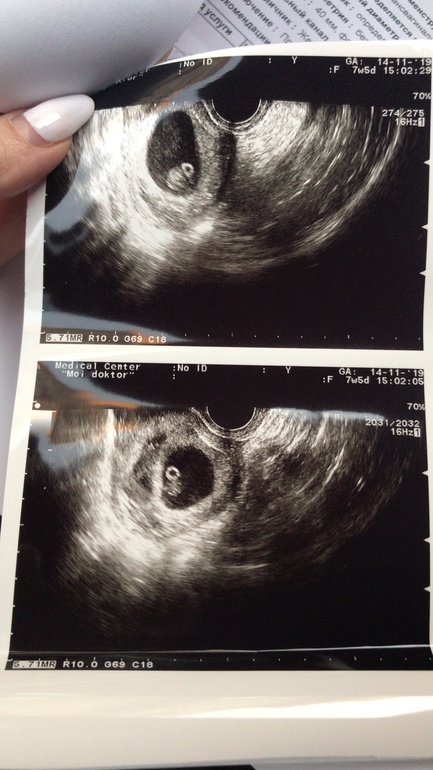

Сходила сегодня на повторное УЗИ. Сказать что я в шоке, это ничего не сказать.....у меня ДВОЙНЯ!!!!!!! 👬

Две недели назад было одно плодное яйцо. Я просто в шоке откуда второй эмбрион🙈

Они в одном плодном яйце похоже) Один за другим, поэтому два разных снимка, их не видно на одном снимке узи) И у автора в прошлых постах сказано, что лопнул 1 фолик и образовалось 1 ЖТ.

Написано что два разных плодных яйца, врач сказал что могли из одной яйцеклетки. И могут быть разнополыми🤷♀️

Сказали что не факт🤷♀️ В заключении дихориальная двойня, могут быть разнополыми

Первое узи я делала в 5,3 акушерских недель, подтвердить что Б маточная. Было одно плодное яйцо, ещё пустое, ЖМ даже видно не было. Потом пошла на 7,5 акушерских и вот два яйца 24мм ктр эмбриона 12мм, и второе 23мм ктр эмбриона 10мм. Сердечки бьются❤️❤️

Прошлое узи было 5,3 акушерских недели. Было одно плодное яйцо, без всего. ЖМ даже не нашли🤷♀️ А сегодня 7,5 акушерских недель. И вот двое❤️❤️ Ктр одного 12мм второго 10мм. Как так получилось никто не знает🤷♀️

Не получилось их сразу двоих. Вот отметила. Между ними видна перегородка